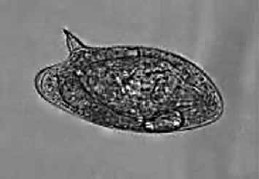

“É uma doença parasitária, diretamente relacionada ao saneamento precário e de grande relevância como problema de saúde pública no Brasil devido à alta prevalência e severidade das formas clínicas. A transmissão ocorre quando o indivíduo infectado, hospedeiro definitivo, elimina os ovos do verme por meio das fezes humanas. Em contato com a água, os ovos eclodem e liberam larvas que infectam os caramujos, hospedeiros intermediários que vivem nas águas doces”.

Observe, a seguir, a imagem de um ovo deste parasita, que pode ser identificado pela análise microscópica de fezes humanas. Qual é esta doença?